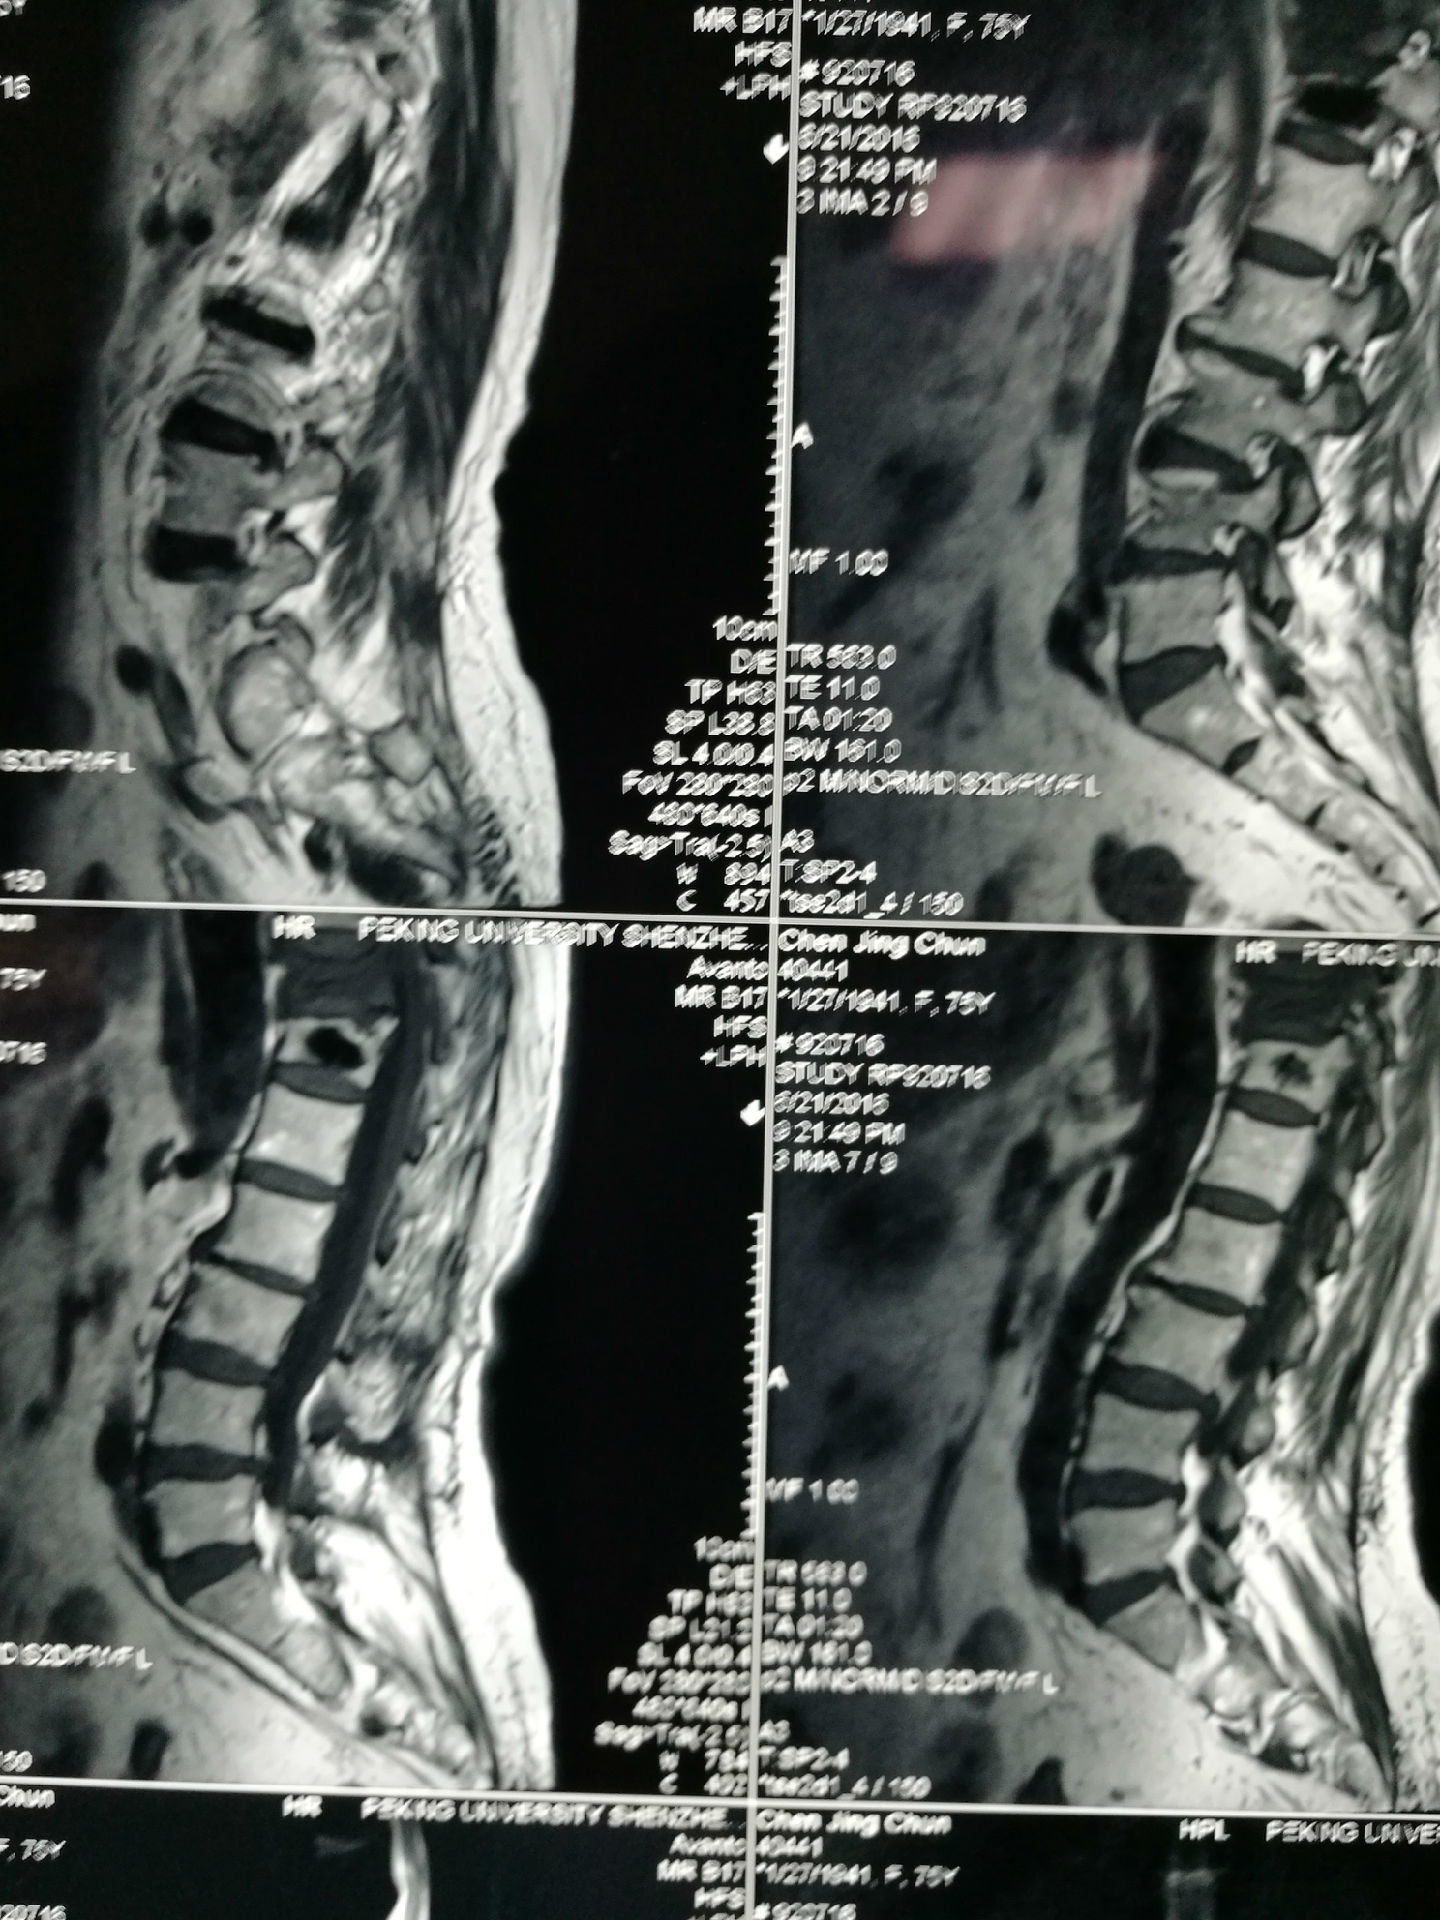

陈XX,女性,62岁,4年前因骨质疏松导致胸12骨折,在外院行微创椎体骨水泥手术,术后患者未规律抗骨质疏松药物治疗,1月前出现胸腰背痛,外院MRI提示胸11椎体(邻椎)发生新鲜压缩性骨折,在我院行微创椎体成形术,术后胸腰背痛明显缓解。